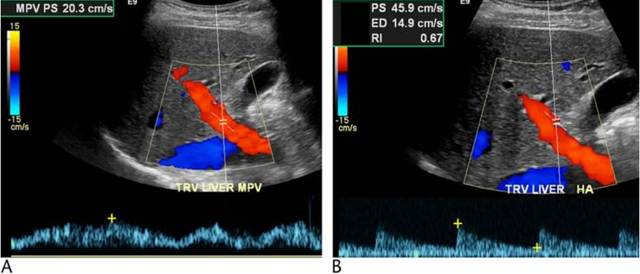

超声检查对自体 肝脏门静脉及肝静脉的评估以及移植肝肝动脉检测应用较为广泛。然而鲜为人知的是,即使自体肝肝动脉流速及频谱的测定对于发现肝脏潜在性病变及…